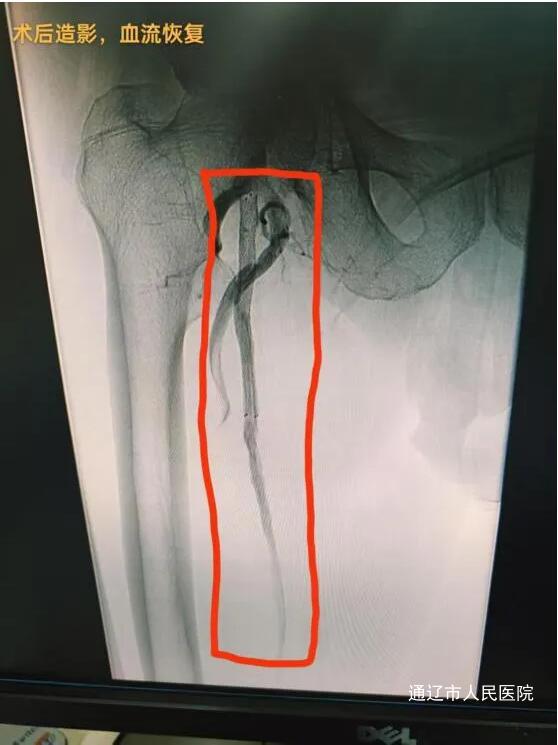

患者,男性,79岁。术前检查发现,其双侧下肢动脉广泛存在动脉粥样硬化,多处混合及钙化斑块致使管腔轻至中度狭窄,右侧股动脉更是出现长达20cm的闭塞段。患者自述,自2022年起就饱受双下肢间歇性跛行的困扰,症状逐年加重。一个月前刚接受左侧髂、股、腘动脉支架置入及下肢动脉PTA。面对这一复杂病情,我院血管肿瘤介入科魏东升主任团队迅速行动,凭借丰富的临床经验与严谨的专业态度,精心制定了个性化的治疗方案。手术由梁羽副主任医师主刀,那日苏、张贺然医师担任助手。手术过程中,医疗团队展现出了高超的技术水平与默契的协作能力。他们通过逆行穿刺左侧股总动脉,精准操作导丝穿越病变区域,完成正逆向开通会师,并在远端成功放置保护伞。随后,启用JetStream旋切系统,将斑块切削并吸出体外,实现血管减容,之后配合药物球囊扩张,结合药物洗脱支架置入,成功打通患者堵塞的血管。术后第二天,患者便能下地行走,间歇性跛行症状明显改善,手术取得了显著成效。